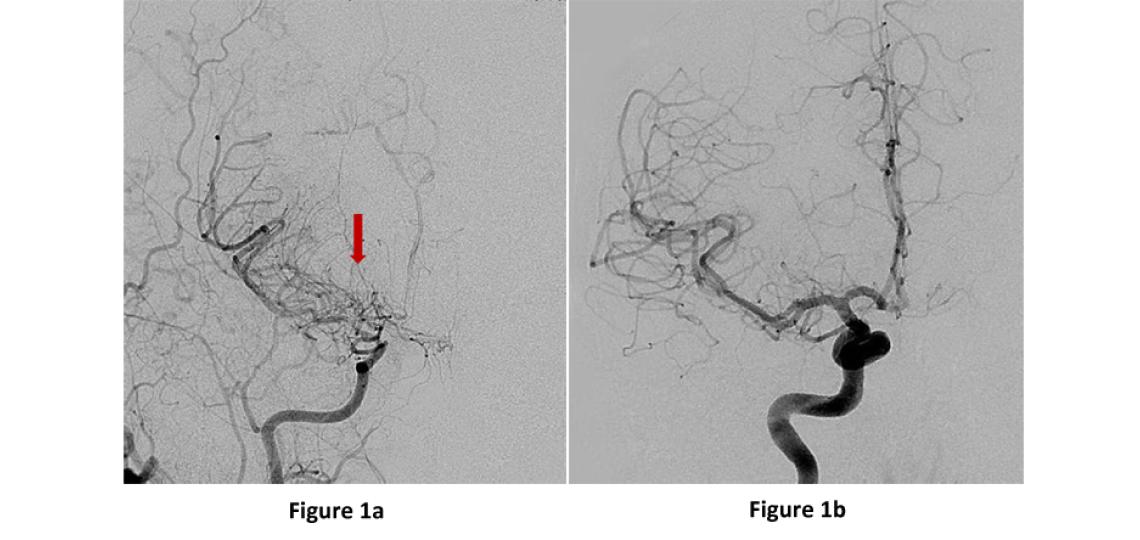

Moyamoya disease is a rare, progressive cerebrovascular disorder caused by the shrinking of major brain blood vessels resulting in decreased blood flow to certain brain regions and eventually can lead to stroke. The term moyamoya was coined by the Japanese physicians who discovered it and means “puff of smoke” which describes the appearance of the network of tiny vessels that form at the base of the brain in moyamoya (Figure 1a). Although it was first discovered in Japan and is more common in Asian countries, the disorder has been found in individuals throughout the world including the United States. Moyamoya most commonly affects children and young adults and there is currently no known medical cure, but surgery to increase blood flow to the brain is an effective option.

Figure 1a: AP or front view of a brain angiogram showing the right internal carotid artery narrowing into the small tangles of moyamoya “puff of smoke” vessels (red arrow). Figure 1b: A normal angiogram for comparison.